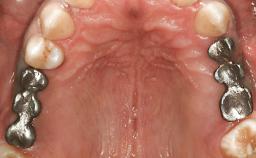

In February 2002, a 31-year-old non-smoking male patient was referred by his dentist after the fracture of the crown of the maxillary right second premolar, tooth 15. The fracture line was located apically to the gingival margin, particularly on the palatal side. Radiographic examination revealed the presence of a previous endodontic treatment with a non-ideal apical seal. There were no signs of periapical osteolysis. The level of the interproximal bone was normal. The patient’s medical history did not reveal any significant findings and he was in good general health.